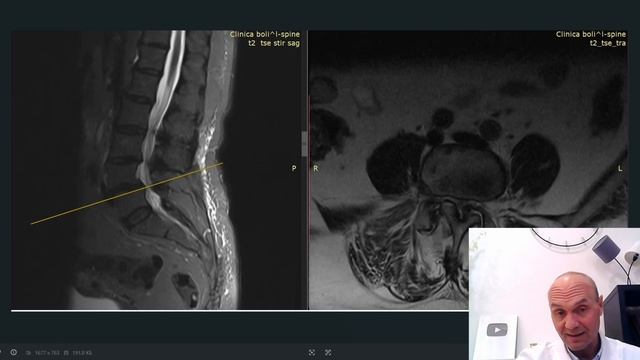

Здравствуйте! Если Ваша проблема трудна для решения и лечение не помогает Вы можете связаться с нами онлайн. Как это работает? Для записи позвоните по телефону: 7484221-00-00 Администратор расскажет вам куда прислать снимки и данные исследов..., видео от 2026-02-26 загрузил на rutube bezboli...